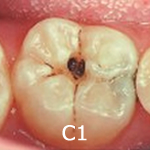

C1(象牙質に達しないむし歯)- 歯の表面のエナメル質のみに穴が開いている状態です。一般的に痛みなどの自覚症状はありません。ただ、放置すると進行してしまいますので抑制をはかり経過観察するか、もしくは削って詰める治療を行います。削る部分は最小限ですみます。